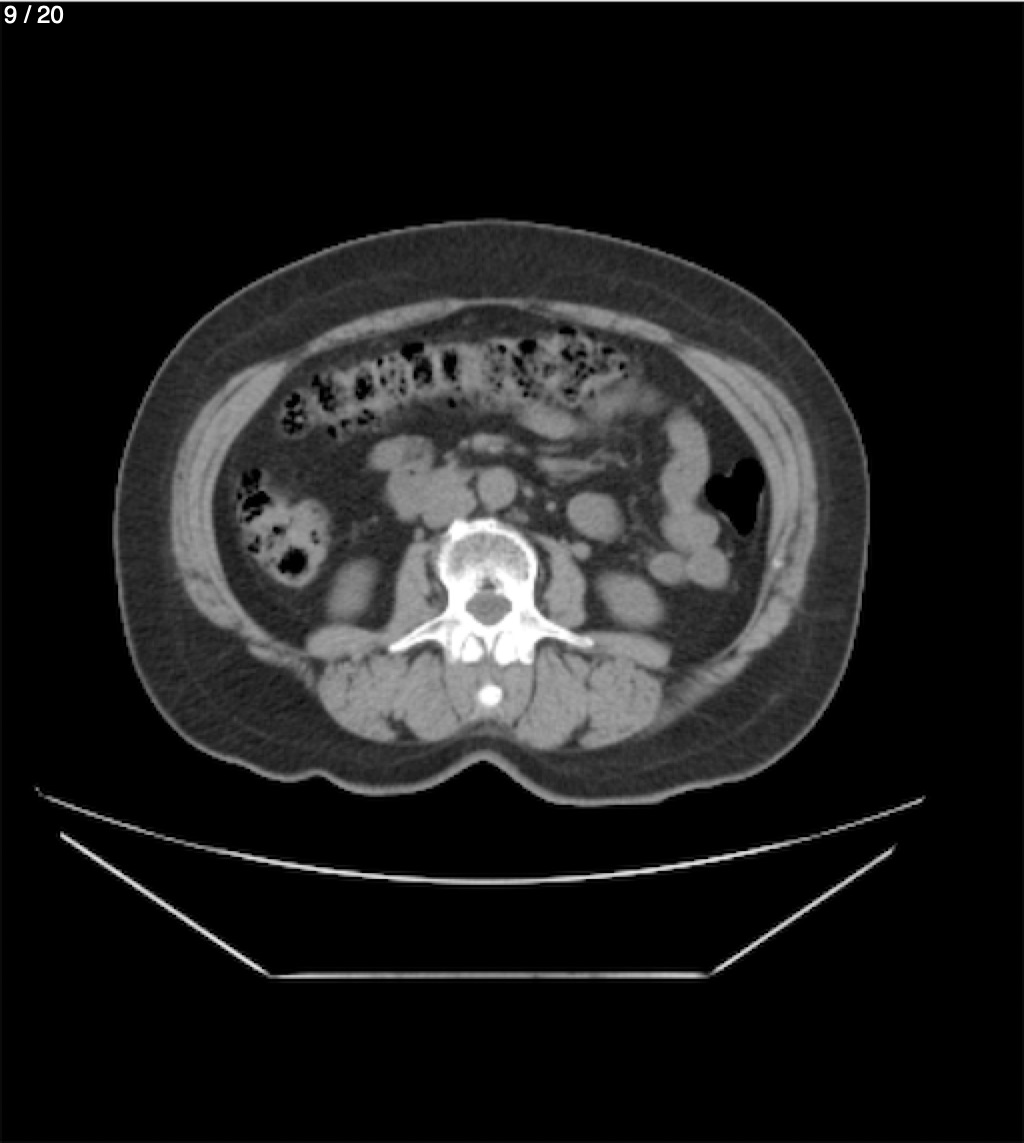

Maria Enrique Giron Dominguez63A - T.C Abdomen Simple